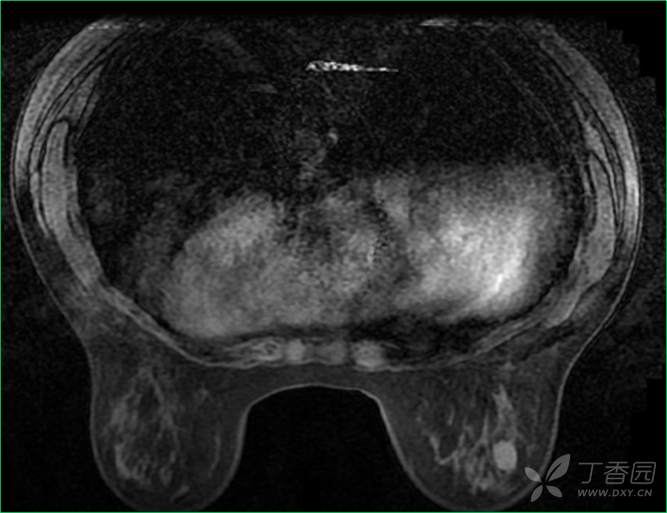

乳腺动态增强MRI检查

T2WI脂肪抑制序列

乳腺动态增强MRI检查(钆布醇)

T1WI增强早期(第二时相,116s)

T1WI增强晚期(第八时相,364s)

3、乳腺MRI显示:右乳外下象限T2WI呈等信号病变影,大小约(14)mm×(10)mm×(15)mm,肿块为卵圆形,边缘模糊;内部强化不均匀,边缘环形强化为主;TIC曲线初始相呈缓慢强化,延迟期呈持续型;DWI呈等信号显示不清。BI-RADS 4类。

诊断意见及建议:超声、X线检查及乳腺MR检查提示,右乳外下象限肿块,呈等密度,边界清楚,形态规则,周边见血流,DWI呈等信号,以上征象皆提示肿块为良性,纤维腺瘤可能性大。